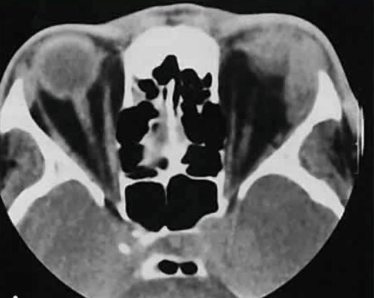

Вид боли При наличии этих болезней возникает простреливающая боль в пояснице и в левом боку. На вдохе неприятные ощущения могут усиливаться, настает покалывание в области левого подреберья. В запущенных стадиях болезней легких боль может быть опоясывающей и простреливающей, отдает в левый бок и низ поясницы. Локализация Неприятные ощущения нарастают в области грудины, отдавая в поясницу. Если же причина не связана с патологиями левого легкого, учащенного дыхания, посинения губ и повышения температуры не отмечается. Диагностика Как правило, болезненность поясницы при наличии заболеваний легких, относят к дополнительным симптомам, которые проявляются при первичном осмотре пациента. Дальнейшая диагностика может включать такие средства как:

- Рентген снимок легких – показывает наличие очагов воспалительного процесса.

- Развернутый анализ крови, анализ мочи.

- Анализ мокроты на выявление типа возбудителя – помогает подобрать наиболее оптимальные варианты лечения.

- МРТ грудной клетки – используется в особо запущенных случаях, когда болезнь поразила более 50% объема легкого.